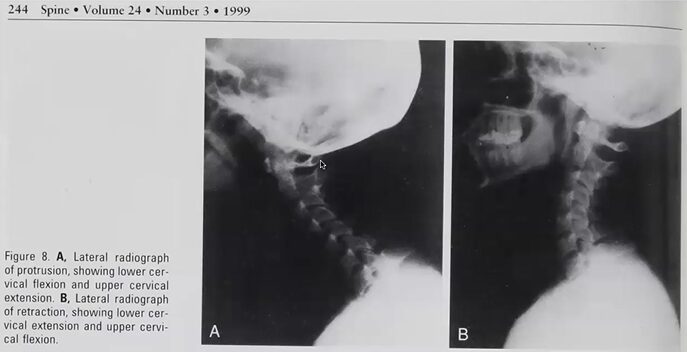

で、反復の運動検査で、retractionのover pressureですね、ちょっとretractionって、このね、顎,これ引いた状態なんで、cからd、

これ、cはアゴ出し動作、dはアゴを引いた動作。retractionの動作って、

このretractionの顎を引いて、反復の運動をやりました。

ちなみにこれ、顎出していると、頸椎が,下頚椎が屈曲、上位頚椎が伸展、で、

顎を引くと下位頚椎が伸展の、上位頚椎ってわかりづらいですが、屈曲方向に行くって、このコンビネーションになってきます。